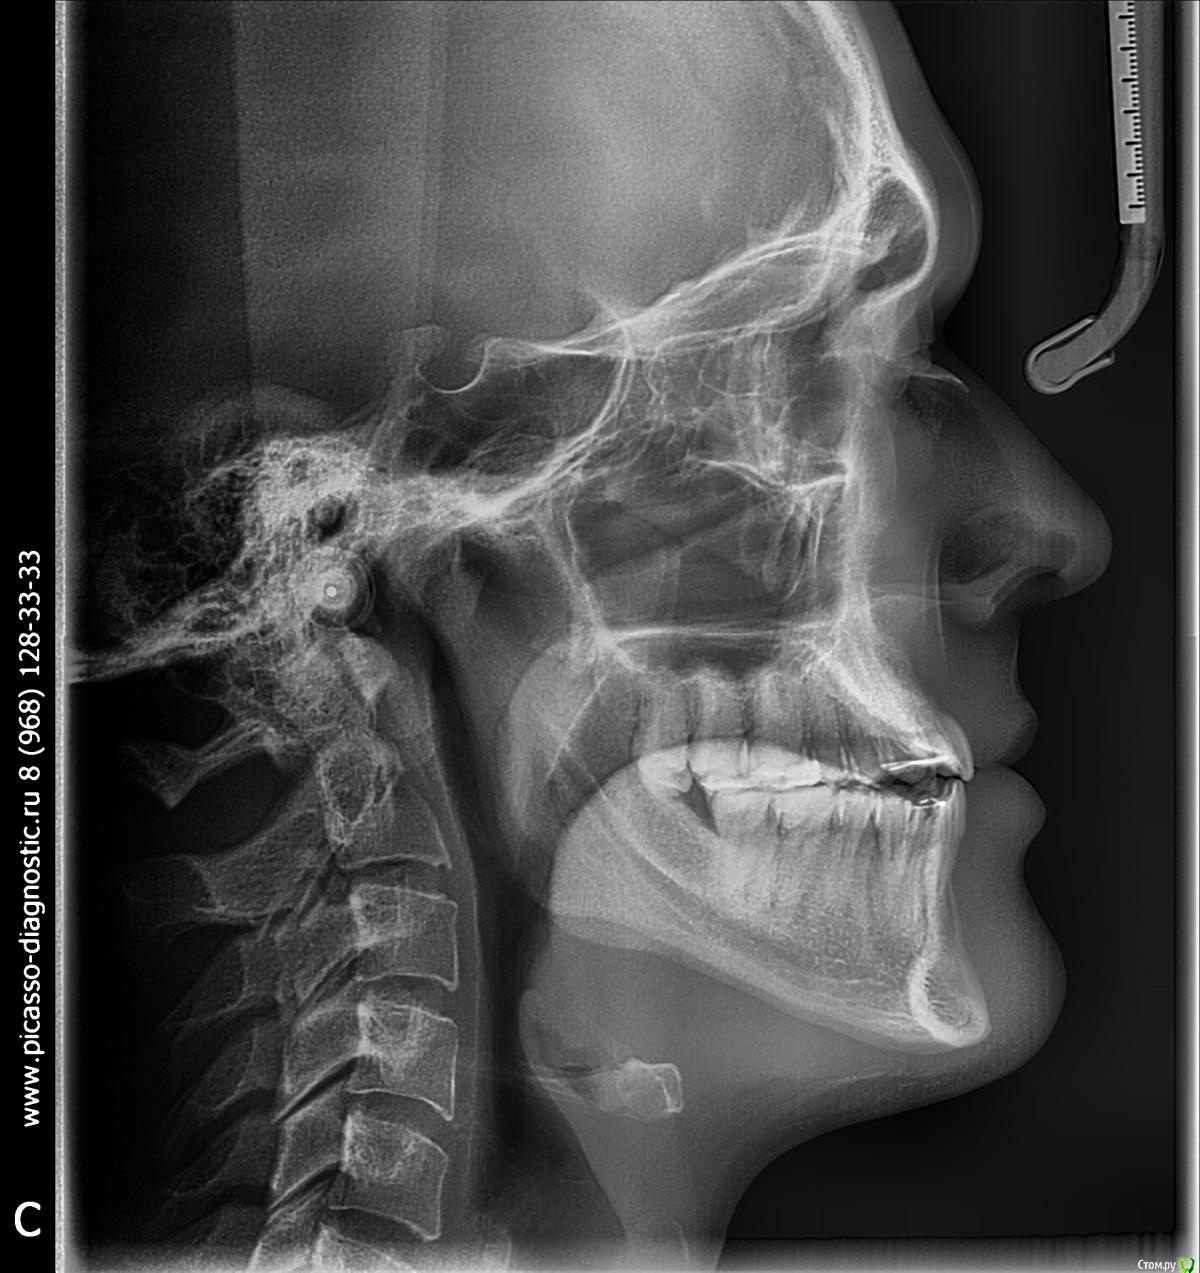

Что предпринять? (Скелетный 3 класс, перекрестный прикус, множественная рецессия, проблемы с ВНЧС)

Здравствуйте, мне 29 лет, хочу остаться со своими зубами и не угробить ВНЧС.

С 16-20 лет проходил лечение у ортодонта (2 года расширитель на верхней челюсти, 2 года брекеты). Итог - получили, так называемый камуфляж (как я сейчас понимаю).

В данный момент ситуация усугубилась, основные проблемы - множественные рецессии и хруст в ухе при глотании.

2 ортодонта посоветовали два разных подхода к лечению:

1ый Операция и только она. На вопрос поможет ли это устранить рецессию, был ответ, что вам никто не скажет, но для проведения операции нужно будет вернуть все зубы в прежнее положение.

2ой Провел диагностику, ТЭНС терапию, сделал капу на нижнюю челюсть (хруст при зевании прекратился, при глотании все равно слышно), про  рецессию было сказано, что некоторые зубы получают неправильную нагрузку, но причина именно множественной рецессии не в прикусе. Дальнейшие предложении - устранение перекрестного прикуса с помощью брекетов или оклюзионного протокола.